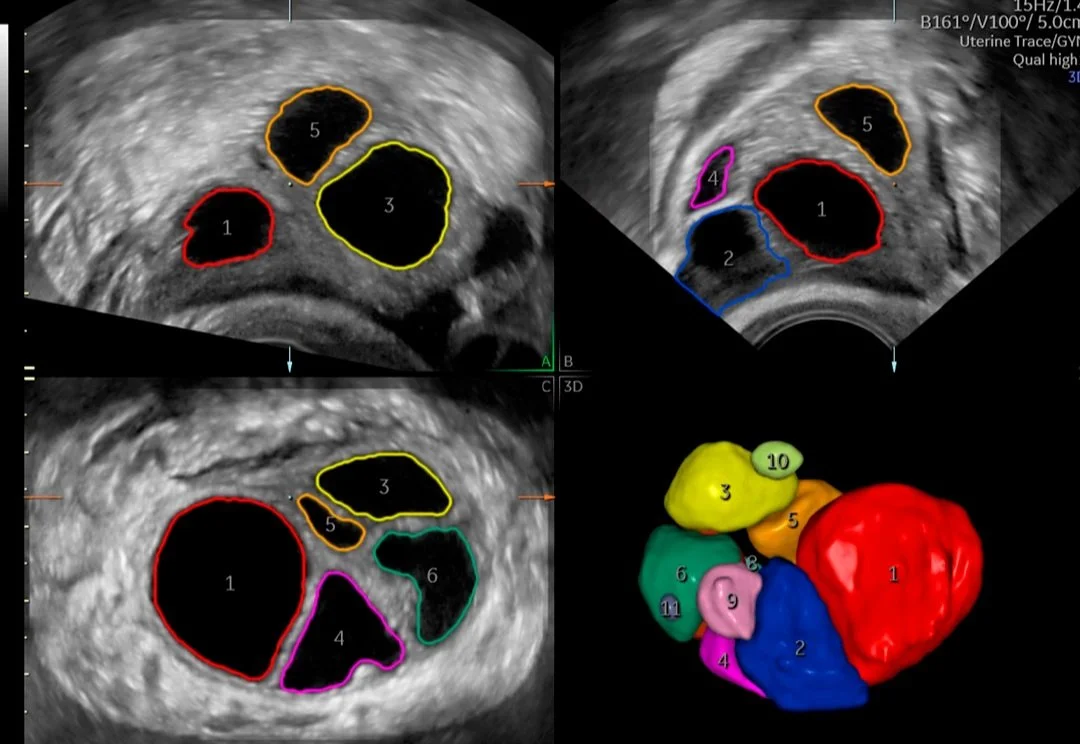

Ginecología

A menudo, la ecografía es la primera línea de defensa para diagnosticar afecciones ginecológicas. El dolor pélvico, el sangrado postmenopáusico, la disfunción genitourinaria y la infertilidad pueden ser síntomas confusos y preocupantes para sus pacientes. Necesitan respuestas y confían en su experiencia para obtener un diagnóstico y tratamiento precisos.

Medicina reproductiva asistida

Entendemos el impacto que tiene la infertilidad en la vida de sus pacientes y en su práctica. Por este motivo, los sistemas de ultrasonidos Voluson superan continuamente los límites de la adquisición de imágenes para ofrecerle herramientas sencillas e innovadoras que le ayuden a usted y a sus pacientes a vivir el sueño de un embarazo próspero.